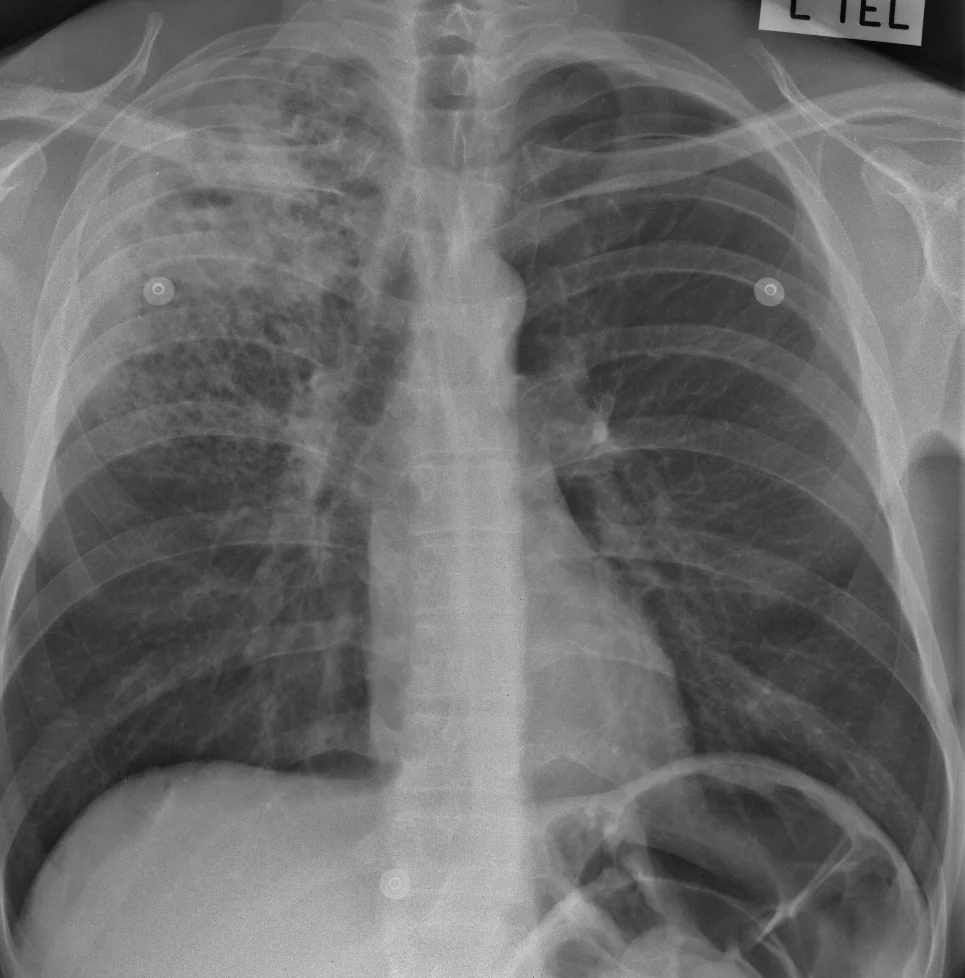

FIND: A huge number of tiny densities are scattered through both lungs. There is a circular dense line in the apex of the right lung. The right lung hilum is higher than normal. No other abnormality is seen.

IDENTIFY: A close-up shows that the lung looks as if it is made of thousands of little dots, or nodules, one or two mm in size. There are so many of them that we can't see the vessels any more. And the abnormality near the right lung apex has the appearance of a cavity with a smooth, thin wall. A high lung hilum usually means that it has been pulled up, either by a lobe which has lost volume or by scarring.

LABEL: There are thousands of tiny nodules scattered through both lungs, and there is a cavity at the right lung apex. The right lung hilum is pulled up but there is no sign of collapse (or atelectasis) of the right upper lobe. So it's likely that there is some fibrous scarring, which we cannot see because of the nodules.

MATCH: In a patient with this history the lung nodules are almost certainly due to miliary tuberculosis. The cavity and the presumed lung scarring also fit with tuberculosis. If the patient was not very ill, the nodules could be due to cancer metastases (although this is very uncommon), with underlying changes of old tuberculosis.

SUMMARISE: Miliary tuberculosis, with apical lung cavity likely due to tuberculosis as well. Right upper lobe scarring causing elevation of the right lung hilum.

Even though cancer is possible, TB would always have to be first on the list of diagnoses in an X-ray like this. Cancer would only be considered if TB could not be proven with sputum analysis and bood tests.

Note that this case is a little unusual, in that military TB is usually seen in primary infection, but this patient is an adult; he also has a lung cavity which is a sign of secondary tuberculosis. This reminds us that diseases don't always follow the rules, especially TB which is changing in the era of increased drug resistance and the effects of HIV/AIDS.